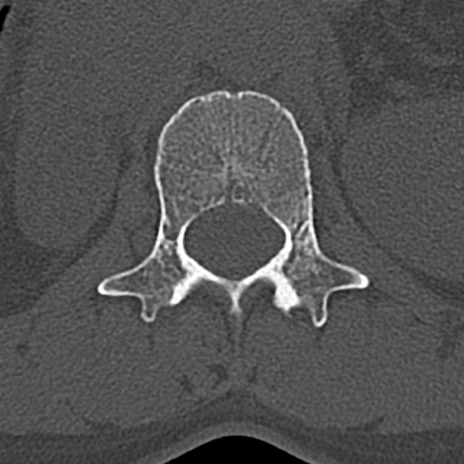

腰椎CT

横断像と矢状断像